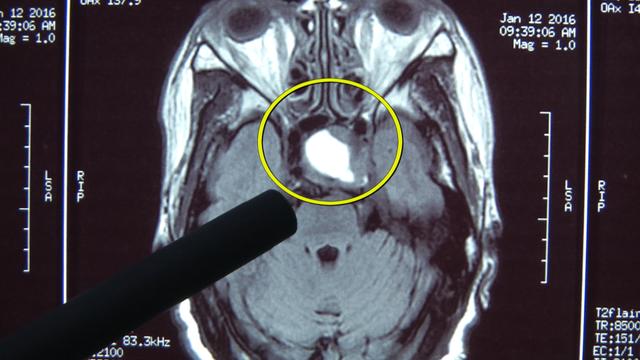

专家解释,问题出在赵女士的大脑内,里面有一个叫脑垂体的东西,长了肿瘤,导致分泌出来的生长因子增多,刺激了赵女士的肢体和内脏变得粗壮肥大。别以为这病没啥大不了,其实还会致命:心脏肥大瓣膜闭合不严,容易造成心衰死亡。

赵女士的手脚和脸型明显都偏大,记者用手对比以下,发现1米6的赵女士,不但手掌比记者的大,手指头也粗了许多。翻开赵女士以前的照片,对比后可以看到,赵女士的脸型也扩大了一圈。不仅如此,CT显示,赵女士的脏器也比常人大,你看这心脏都越过了脊柱,一部分都跑到了胸腔右侧。